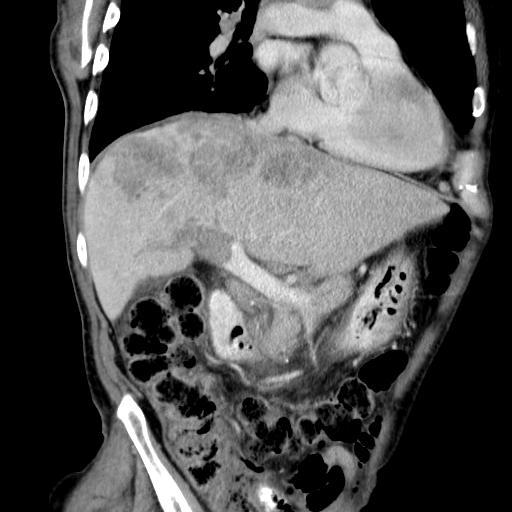

Здравствуйте, коллеги! Мужчина около 70 лет. Жалобы: слабость, утомляемость около 3х месяцев, чувство тяжести на желудке после еды. Анамнез: онко не было. С вышеописанными жалобами обратился ко врачу, сделали ФГЭДС - признаки гастродуоденита, по биопсии - N. В течение 2х последних недель существенно похудел и начал желтеть. Выполнена МСКТ

А как насчет холангиокарциномы с тромбозом воротной вены и мтс в средостение, лимфоузлы брюшной полости и забрюшинного пр-ва?

Внимательно пересмотрел, признаков характерных для ГЦР не нашел (кроме тромбоза). Согласен с холангиокарциномой, ещё бы отсроченную фазу, для печени минут через 12-15 .

Для холангиокарциномы характерно гиперденсивность, в отсроченную фазу, за счет аффинитета к контрастному веществу.

Ну я уж, собственно, ответил. Холангиокарционома накапливает контраст, альвеококк - нет. И потом, холангиокарцинома, как правило, вызывает обструкцию желчных протоков, так что проксимальнее обструкции мы увидим их расширение - очень яркий признак на КТ.